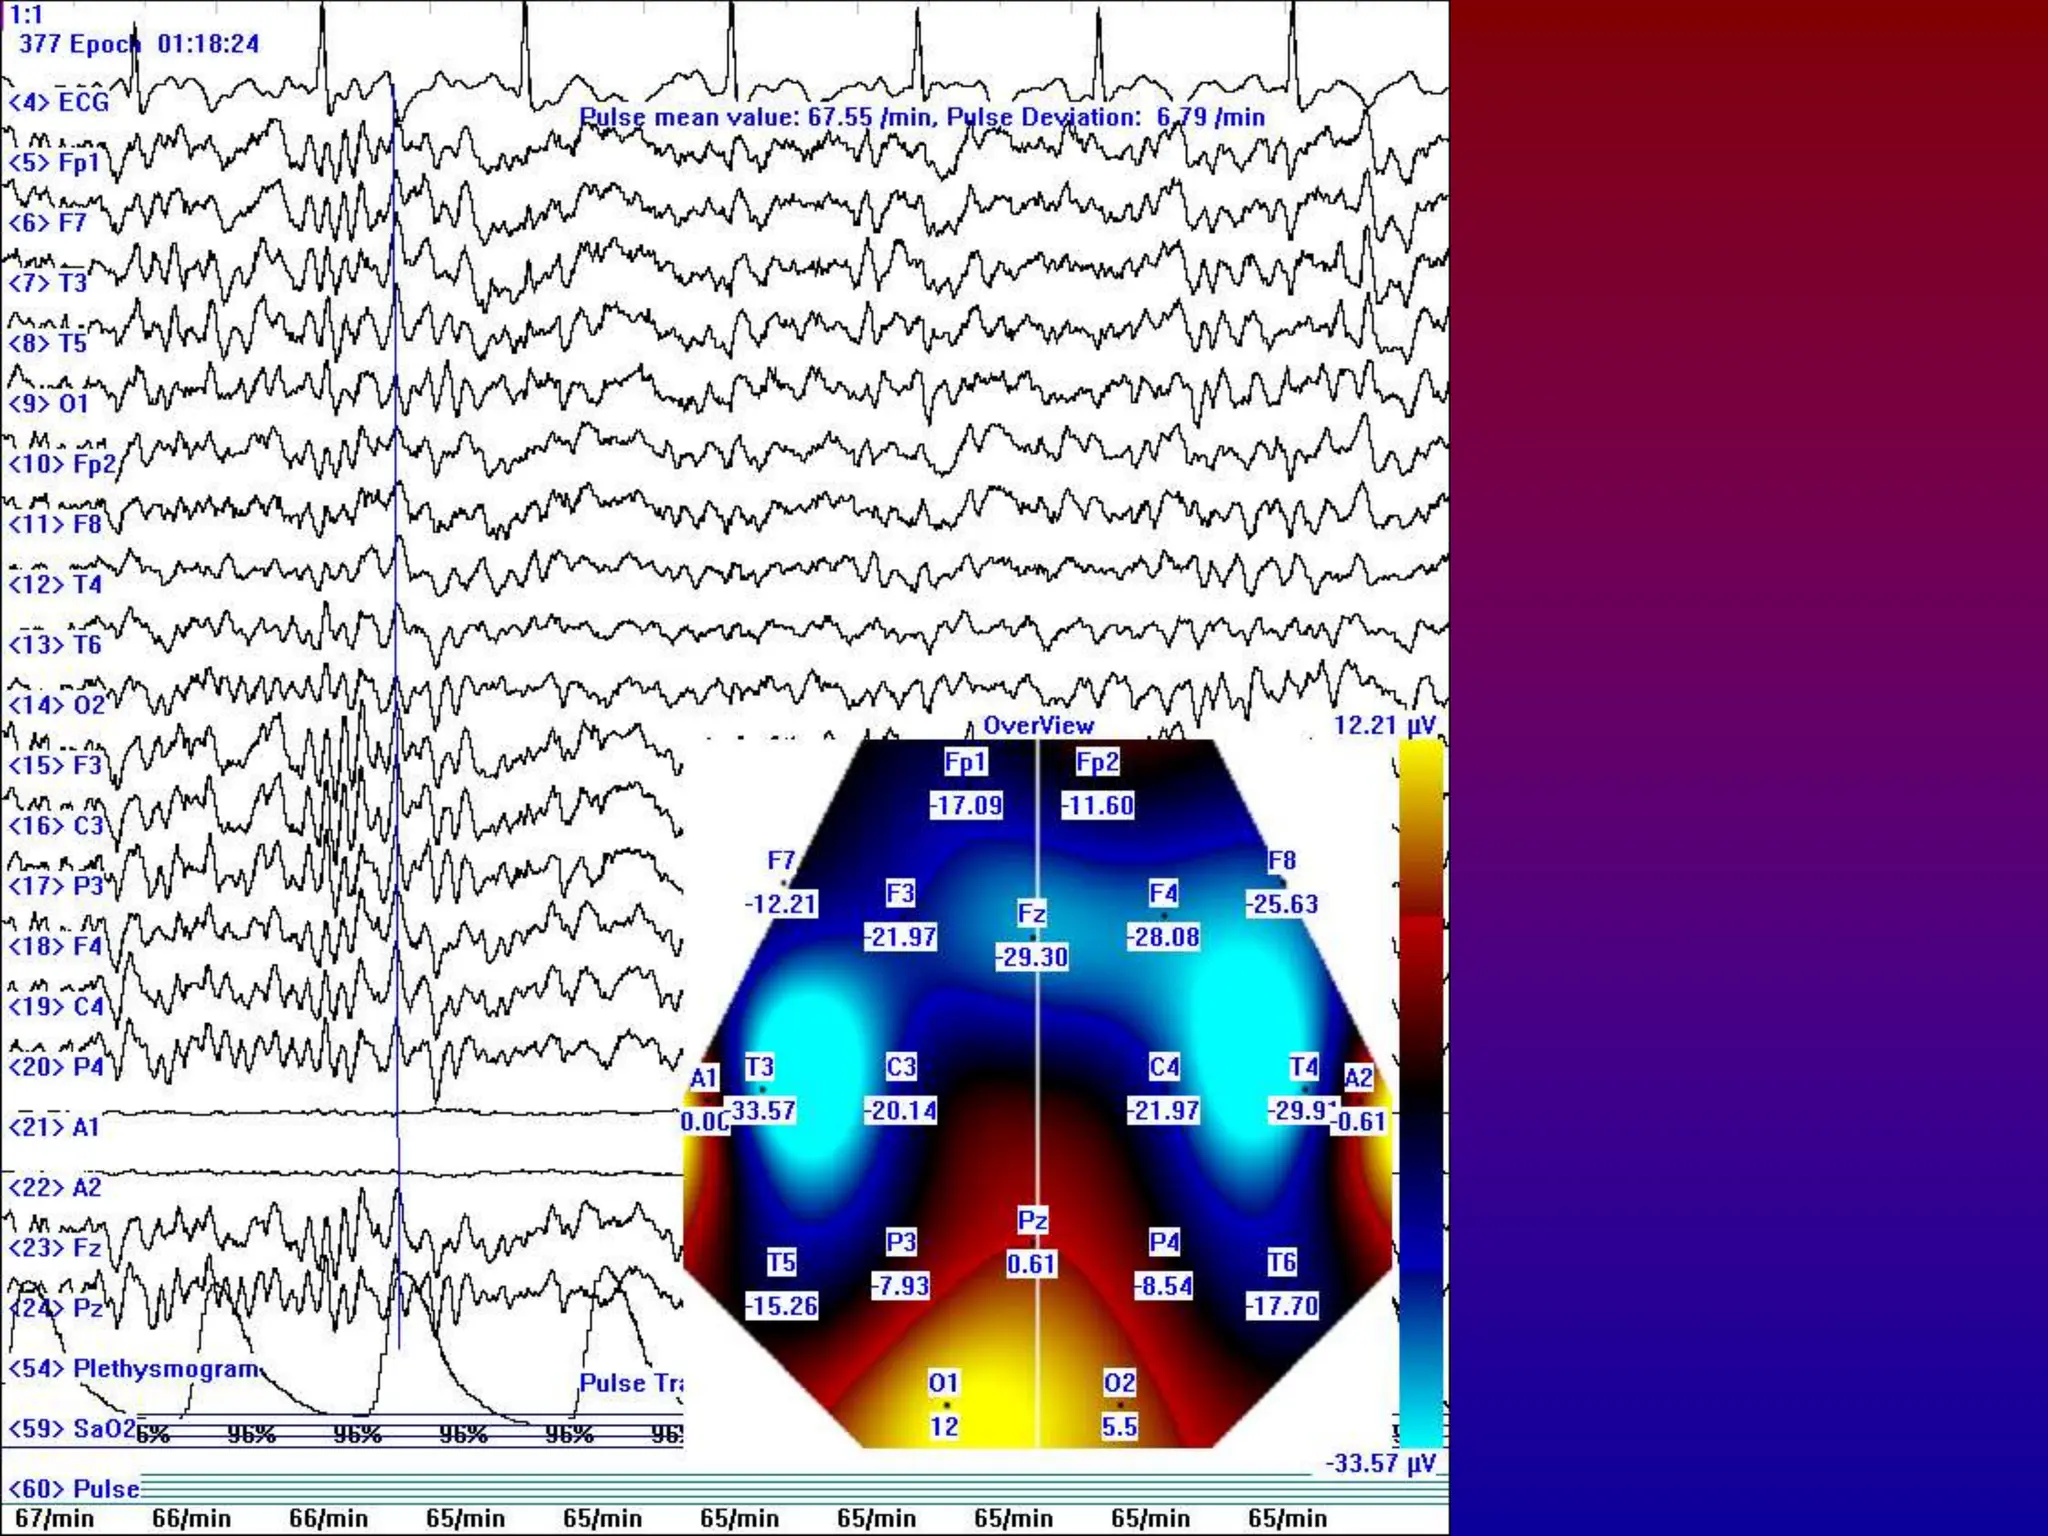

• To get better information about neurons

activity it is possible to use more than two

electrodes, this is used specially in so called

brain mapping, when the result is brain

image with areas of activity and inactivity.

LEONARDO BRAINMAP

EEG and PSG

• Very high-performance up to 256-channel EEG and PSG Recording based on

notebook or PC System and provides clear, sharp traces. The amplifier system

is designed specifically for the EEG and PSG monitoring to satisfy the needs of

the physician's office, hospital, or medical center and combines the latest digital

design techniques with years of amplifier design and manufacturing experience.

• To getbetter information about neurons activity it is possible to use more than two electrodes, this is used specially in so called brain mapping, when the result is brain image with areas of activity and inactivity.

• To standardizeresearch and diagnostic results there is a standard for electrode positioning called 10-20 standard.